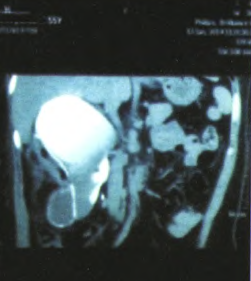

B超检查提示:右肾上极可见一约113mm*88mm囊性结构。 双肾增强CT检查提示:增强扫描提示右肾区囊性低密度影,囊壁钙化,未见明显强化,大小同平扫,周围可见少许强化之肾实质

予完善相关术前准备,查无明显手术治疗。予行腹腔镜下肾囊肿去顶减压术。 术后病理提示:纤维组织囊壁伴透明样变性,囊肿内容物系坏死组织。 术后患者出现持续发热,体温最高达39.3℃,行双肾CT平扫提示肾上极囊肿大小与穿刺抽液前大小相同,无明显缩小,经重新审视病历考虑该患者可能系肾囊肿合并肾上极巨大。肾盏憩室,给予行双肾CT平扫+逆行造影后双肾平扫提示:右肾钙化囊肿减压术后改变,囊肿缩小,张力明显减小,但囊肿壁有卷曲,肾上极较大囊内可见较多造影剂。经科室讨论明确诊断,考虑发热系肾中部钙化囊肿内坏死物质吸收所致,而肾上极“囊肿”为肾盏憩室,遂行右。肾探查术,术中见残余肾组织大小已不足正常肾脏1/6,残余肾组织被囊肿及肾盏憩室挤压变薄,考虑如保留肾脏可能术后发生较多并发症遂行肾切除术,术后标本可见肾盏憩室与肾盂相通,右肾囊肿囊壁钙化并较硬,厚度约1cm。